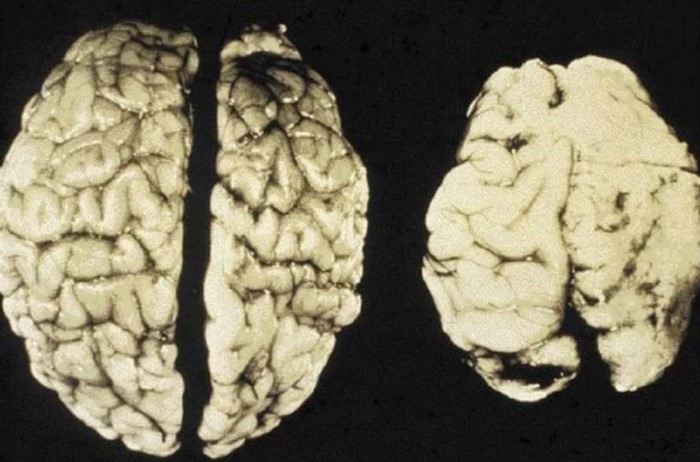

Было выяснено, что чрезмерное употребление алкоголя повреждает мозг. Кроме всего прочего, алкоголь тормозит связь между нервными клетками, в результате чего мышление при опьянении замедляется. Хотя мозг регенерирует снова и снова, он необратимо повреждается.

Алкоголь является нейротоксином. В клетках печени этиловый спирт превращается в ядовитый продукт переработки этанола, ацетальдегид. Соответственно, чрезмерное употребление алкоголя приводит к нарушению кровообращения в головном мозге, гибели нервных клеток.

Заболевание обычно возникает только после многих десятилетий чрезмерного употребления спиртных напитков. Алкоголь пагубно действует не только на клетки головного мозга, но и на нервные связи, что приводит к атрофии клеток. В отличие от болезни Альцгеймера, при этом типе деменции мозг все еще может частично восстанавливаться. Однако выраженная алкогольная деменция необратима.